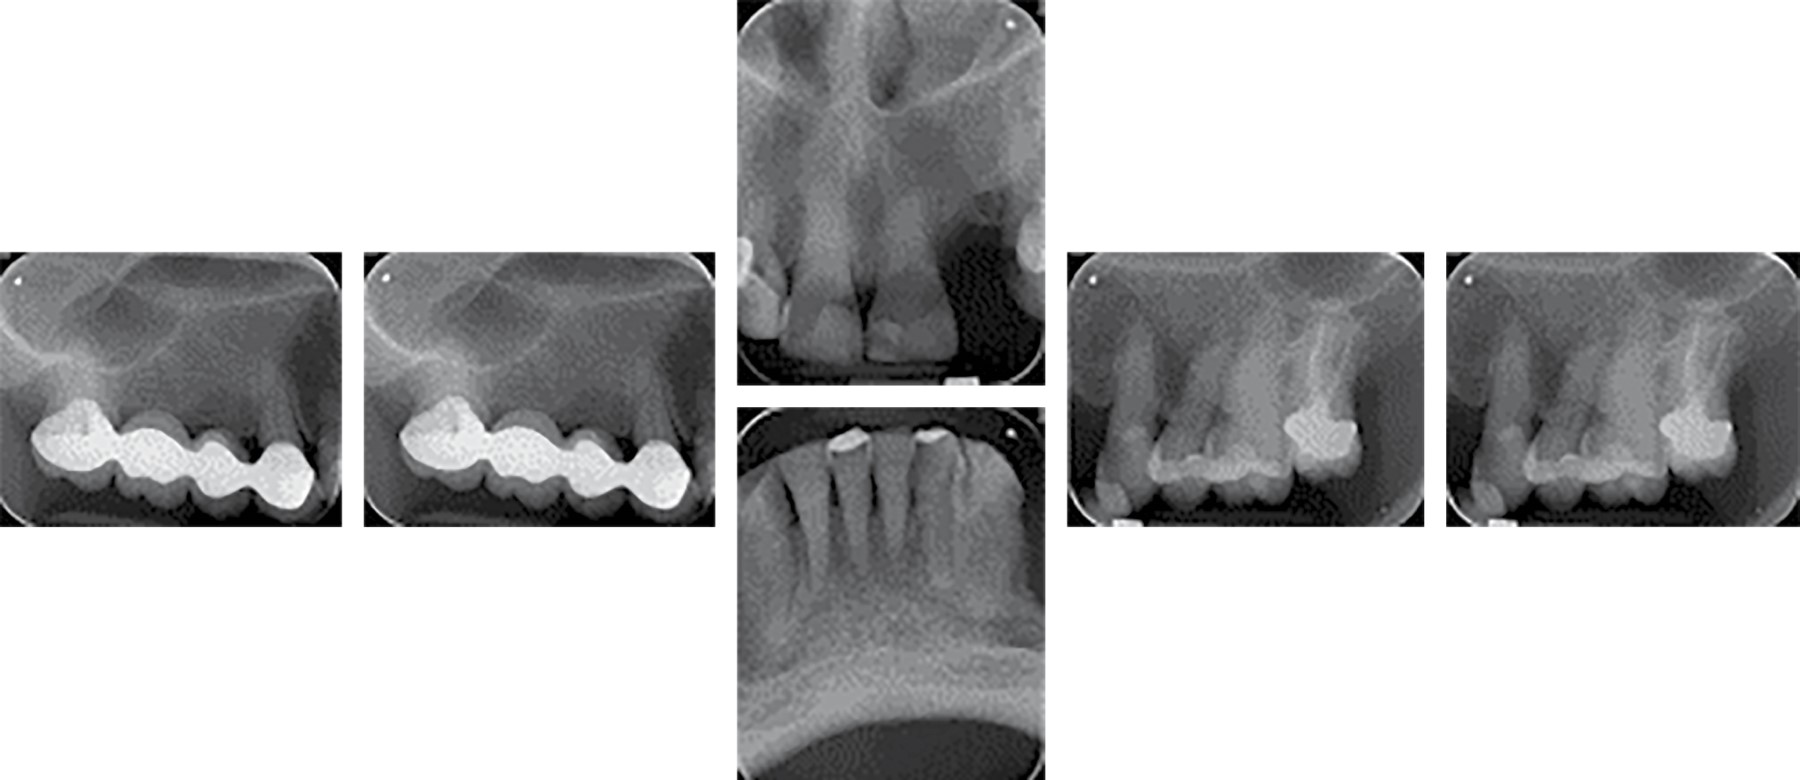

Bisphosphonates are synthetic analogue drugs of pyrophosphates that have a high antiresorptive potency in the bone remodeling cycle. They have in their chemical structure a carbon atom which remains linked to two phosphate groups (P-C-P), their negative charge explains the affinity they have for bone tissue. This clinical report presents the treatment of a patient with a history of osteoporosis, who, due to the use of removable partial dentures in poor condition, caused severe atrophy of the alveolar ridge. Currently, he is prescribed zoledronic acid (bisphosphonates). The placement of dental implants and extractions is contraindicated in patients on bisphosphonate treatment, so an alternative treatment is chosen that consists of a removable polyoxymethylene partial prosthesis and a four-unit bridge with an endocrown-type posterior abutment design. After one year, with 11 months of use of the new fixed prosthesis, the patient did not present dislodgement of the bridge, no occlusal problem was observed, with no absence of increase in the resorption of the edentulous alveolar ridge in the maxilla and mandible, the treatment gave great results both for the general health of the patient and to meet her expectations.

Figure 1